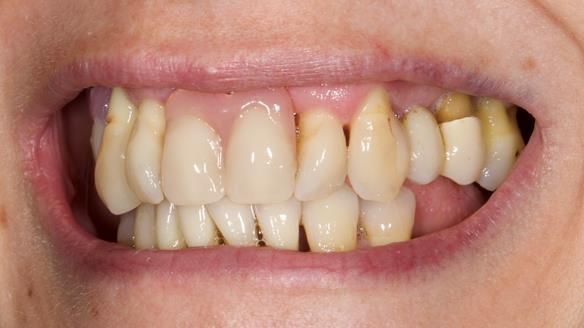

She had previously suffered from generalised periodontitis – stage IV, grade C, currently stable, with reduced attachment across the upper arch.

By the time she came to me, her periodontal condition was stable — but the aesthetics in the upper jaw were very poor.

Dr Syed Abad — my colleague and a Specialist in Periodontics — had successfully stabilised her gum health.

We provided her with an immediate upper denture (Mk 1), followed by a definitive metal-based upper denture (Mk 2). A lower removable partial denture was discussed, to be made only if needed once the upper treatment was complete. However, at review, this wasn’t necessary — Adnana had excellent neuromuscular control and function, even with a shortened dental arch (SDA).